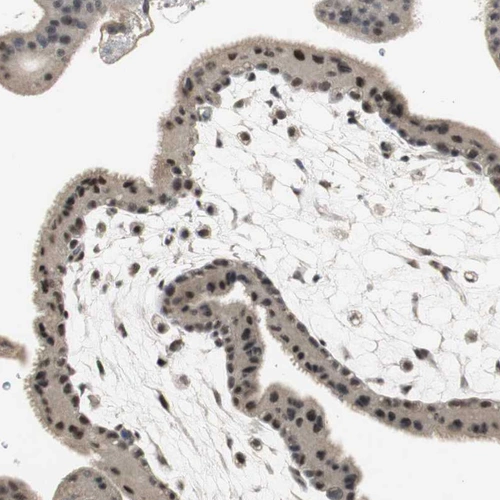

Immunohistochemical staining of human testis shows strong nuclear positivity in cells in seminiferous ducts.